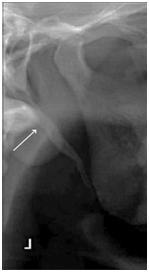

An ESP may be observed in three distinct views on the OPTG images. Type I (Figure 1) reveals an uninterrupted ESP, type II (Figure 2) represents the styloid process being joined to the stylohyoid ligament by a single pseudo-articulation, and type III (Figure 3) consists of interrupted segments of the mineralized ligament, which appear like multiple pseudo-articulations within the ligament.7

Figure 1 Type I, uninterrupted elongated styloid process (Radiograph from More CB & Asrani MK.10)